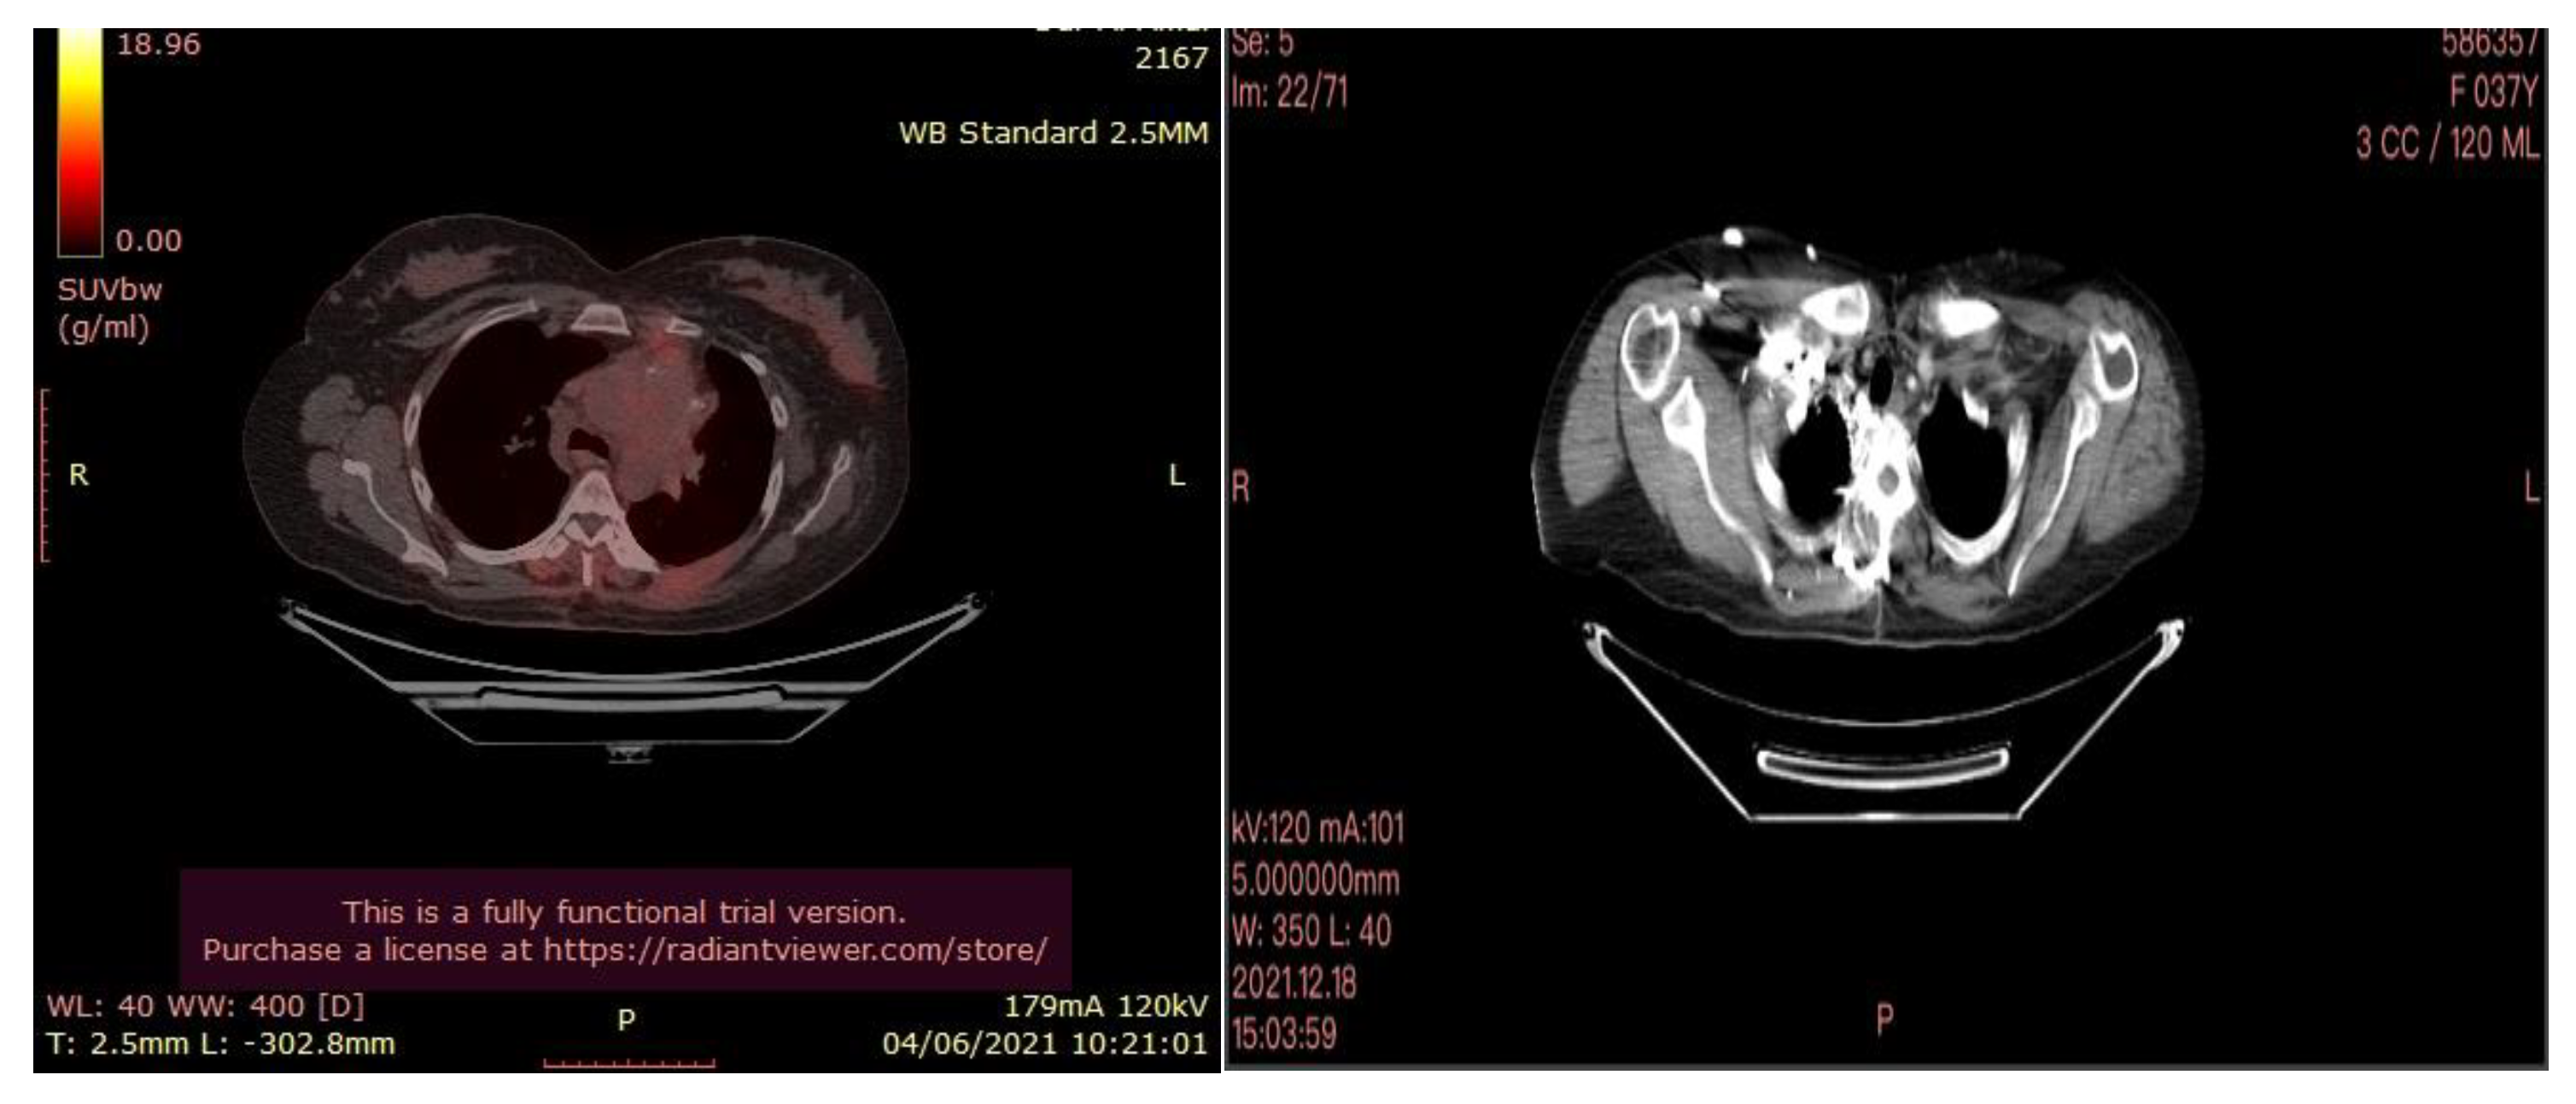

In July 2021, a 60-year-old patient came to our Cryosurgery unit, provided with a CT scan of the chest dated April 2021. The CT scan revealed the presence of a hyper-metabolic lesion with a size of 2.8 cm and involving the right upper/middle lobe related to the neoplastic process. The presence of hypermetabolic lytic bone lesions involving the right proximal femur T-10 and the left transverse process of T-9 was also confirmed, highlighting bone metastasis (Figure 4).

The process for patients with metastatic disease should include abdominal and pelvic CT scans. This is the reason why an abdominopelvic CT scan with contrast was performed in July 2021. There was no evidence of abdominopelvic metastases but always manifestations of diffusion of bone metastases. A specular nodule was noted in the right upper lobe with evidence of bilateral pulmonary nodules, and pleural and bone metastases. The pleural biopsy performed confirmed the presence of metastatic adenocarcinoma.

After three months of the cryoablation, specifically in November 2021, a control CT scan and Pet-CT was performed. An impressive reduction in the size of the tumor is noted (Figure 10).

Figure 4. CT scan (left) and Pet- CT (right) images from April 2021 with evidence of bone metastases. The arrows indicate the tumor’s location.

Figure 10. PET-CT (left) and Ct scan(right) images after cryotherapy in the patient with lung cancer accompanied by bone metastases.